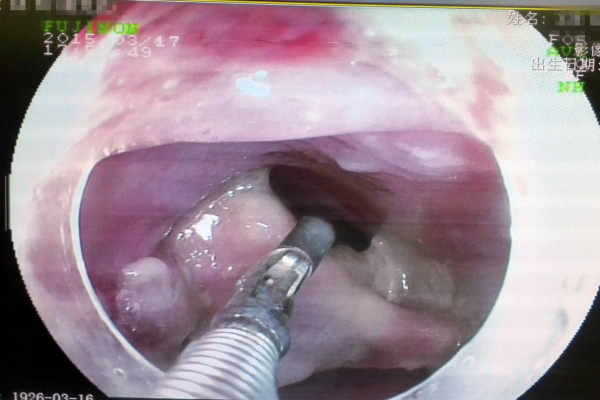

由于手术难度高,风险大,整个病房的医生们也都来了,紧张的手术室里,消化内镜中心的袁海锋主任、黄金锐护士长等人正有条不紊严密配合着,虽然提心吊胆,但每个手术步骤都要做到精准控制,在旁边的医生也都捏了一把汗,“在主刀医生成功取出约3cm*4cm异物(骨头)的时候,手术室里二十几个人不约而同鼓起掌,大家长长地松了一口气”。

内镜视野下谢大爷食管内异物

内镜下异物取出手术